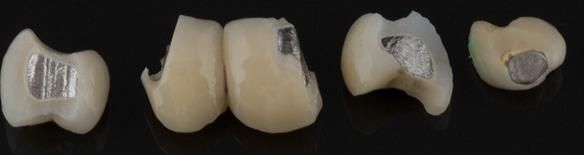

- Generalised Periodontitis; Stage 4, Grade C, Currently Unstable. Risk Factors: Type 1 diabetes. 16, 17 - hopeless prognosis. 14, 24, 26, 27, 34, 37, 44 - guarded prognosis

- Poor marginal fit and poor appearance of crowns and bridgework

The clinical situation and treatment process is shown in detail below with photographs. I (Finlay Sutton) provided the clinical work and Rowan Garstang provided the technical work.